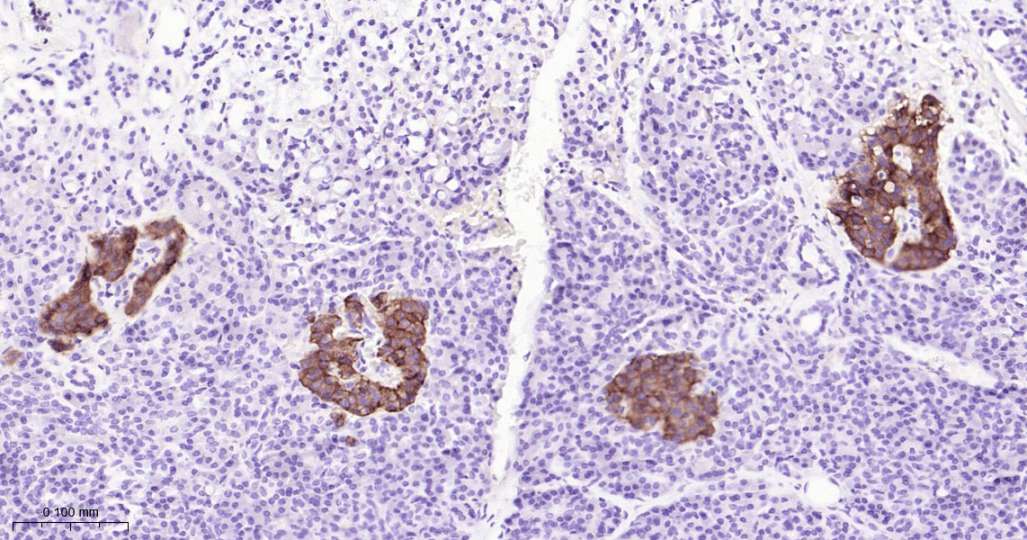

Immunohistochemical analysis of paraffin embedded Mouse pancreas tissue slide using IHC0532 (Somatostatin Receptor 2 Kit).

Immunohistochemical analysis of paraffin embedded Human pancreas tissue slide using IHC0532 (Somatostatin Receptor 2 Kit).

Immunohistochemical analysis of paraffin embedded Rat pancreas tissue slide using IHC0532 (Somatostatin Receptor 2 Kit).